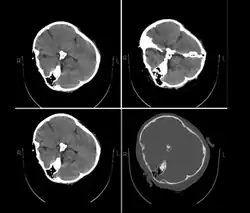

Published hospital pictures show Mahsa Amini bleeding from the ear and with bruises under her eyes. In an 18 September letter, Doctor Hossein Karampour (the top medical official in Hormozgan province), pointed out that such symptoms "do not match the reasons given by some authorities who declared the cause to be a heart attack... (they are instead consistent with) a head injury and the resulting bleeding."[76] This was also confirmed by alleged medical scans of her skull, leaked by hacktivists, showing bone fracture, hemorrhage, and brain edema.[10][77]

A low-resolution copy of an alleged CT scan of Amini post-arrest that was leaked to Iran International.

By 21 September, the hospital had released preliminary CT scans. Government supporters stated the CT scans showed psychological stress caused by a previous brain operation; critics stated the scans showed physical beating and trauma. The Iranian government stated Amini had a brain operation at the age of five.[81]